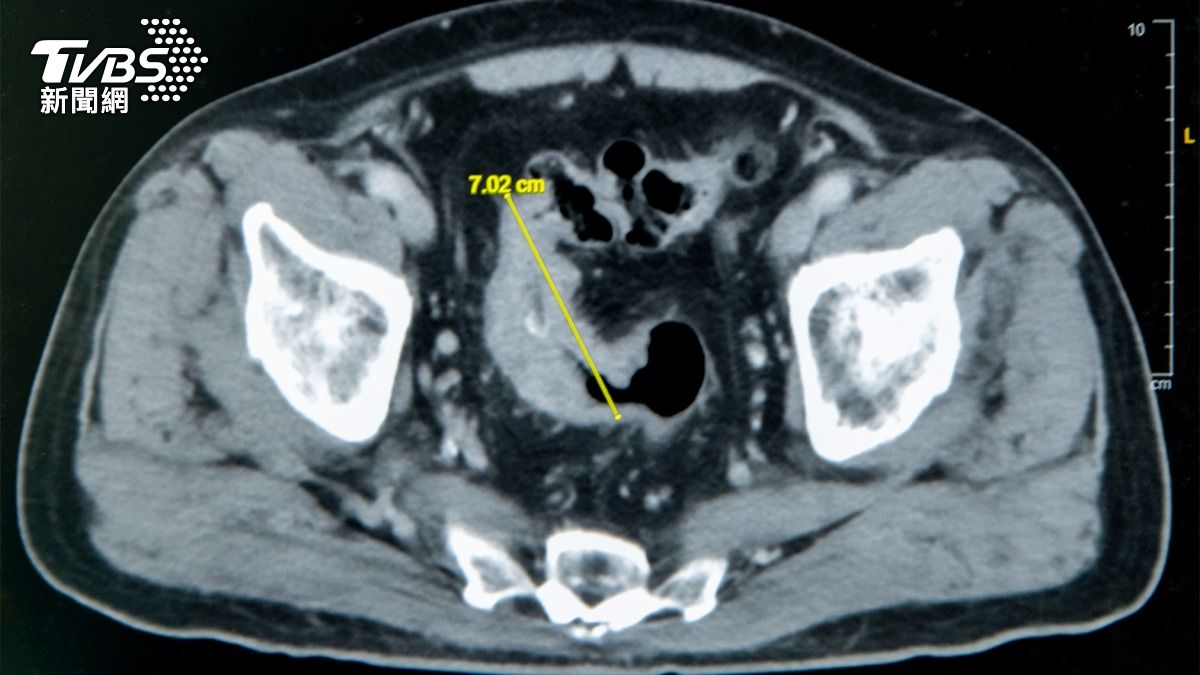

資深媒體人呂文婉以犀利觀點與深厚資歷,長年活躍於各大談話性節目,是觀眾相當熟悉的面孔,私下也常透過社群平台分享工作與生活點滴,吸引不少粉絲關注。今(28)日她突在社群發文報平安,卻同時透露身體亮起紅燈,

中國時報